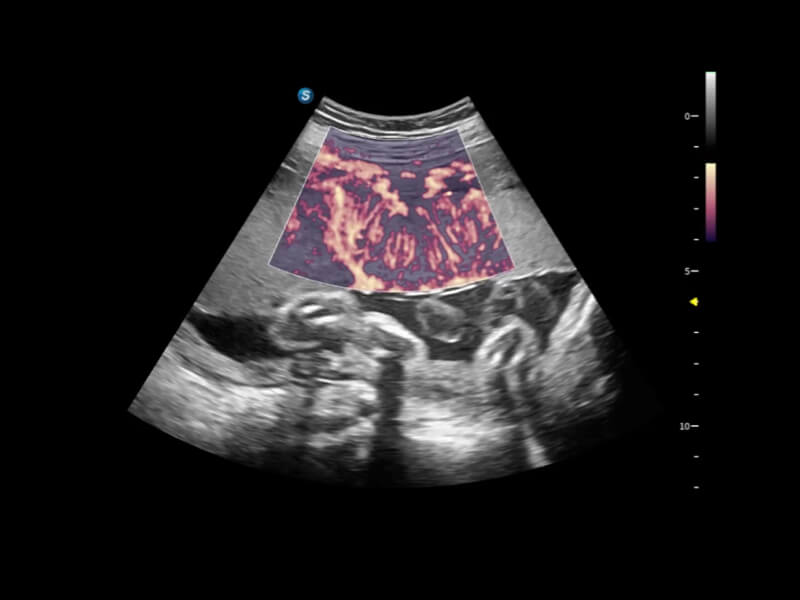

豐富的血流動(dòng)力學(xué)檢測(cè)技術(shù),可在不同醫(yī)療場(chǎng)景中高效捕捉血流信號(hào),助力臨床診療。

在傳統(tǒng)血流的基礎(chǔ)上優(yōu)化掃查和算法策略,能夠更好的抑制組織信息,提煉紅細(xì)胞運(yùn)動(dòng)信息,得到更高幀頻,高靈敏度和分辨率的血流信號(hào),還原更真實(shí)的血流動(dòng)力學(xué)。

通過光照模型,使二維血流顯示出立體的效果,增加血流的敏感性、成束性,減少外溢??梢院推渌煌难骷夹g(shù)聯(lián)合使用,融合不同技術(shù)的優(yōu)勢(shì)。輕松應(yīng)對(duì)微小血管,增強(qiáng)血流的立體效果,提升視覺敏感性。

通過創(chuàng)新的Matrix E自適應(yīng)濾波算法,能有效濾除軟組織和噪聲信號(hào),最大限度保留超低速微細(xì)血流的信號(hào);結(jié)合超長時(shí)間域算法,極大提升細(xì)微血流的敏感性和空間分辨率,更真實(shí)的反應(yīng)組織、包塊的血流灌注情況。